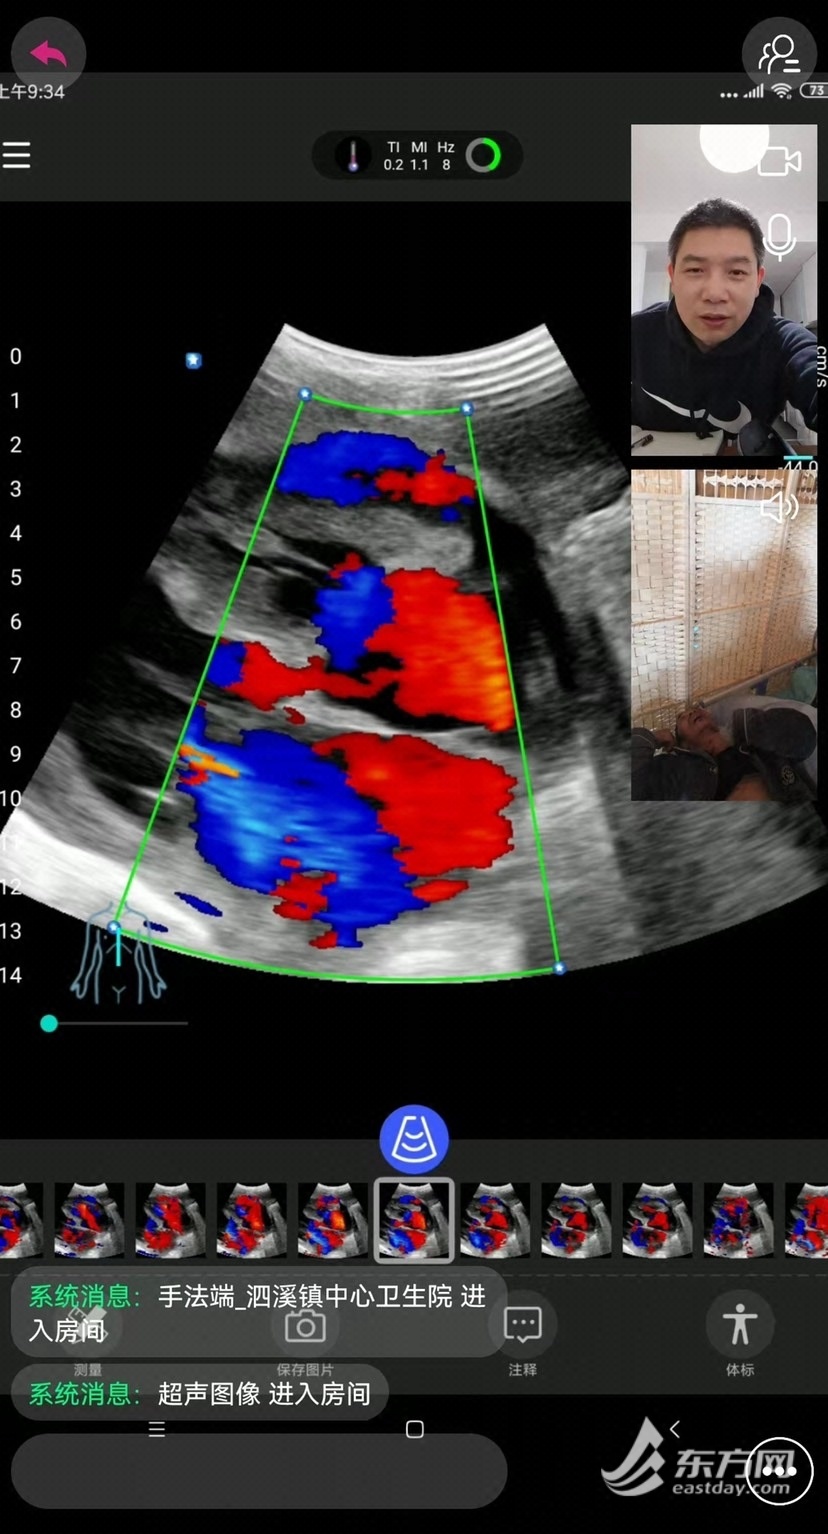

王医生带着掌上超声机器来到患者家里,和彭主任进行了实时的连线会诊。超声机器扫描过的位置,图像直接呈现在彭主任的手机上,“左心增大;室间隔和心尖部心梗后改变;二尖瓣重度反流;左室收缩功能减退;心包腔积液……”得益于远程及移动超声技术的支持,这名距离上海600公里外的浙江和福建交界处一个偏僻山村的患者,在家里及时得到了超声检查,也明确了患者呼吸困难的根本原因:心功能衰竭和心包积液,为后续的治疗指明了方向。 这并不是唯一受益于远程超声支持的患者,近半个月来,泰顺县仕阳镇卫生院、横坑村卫生院、柳峰乡卓宅村等13家泰顺乡镇卫生院和村卫生室的医生先后连线上海市第十人民医院超声医学科,彭成忠、孙丽萍、张一峰、郭乐杭等超声专家们,有的隔离封控在家,有的在医院闭环管理,但依然能够使用身边的电脑或手机,为患者进行了远程实时掌上超声会诊达30余例,肝血管瘤、肝内胆道扩张、胆囊结石、肾结石、肝肾囊肿、前列腺增生等,一个个远程实时会诊帮助当地患者做出了及时的诊断。